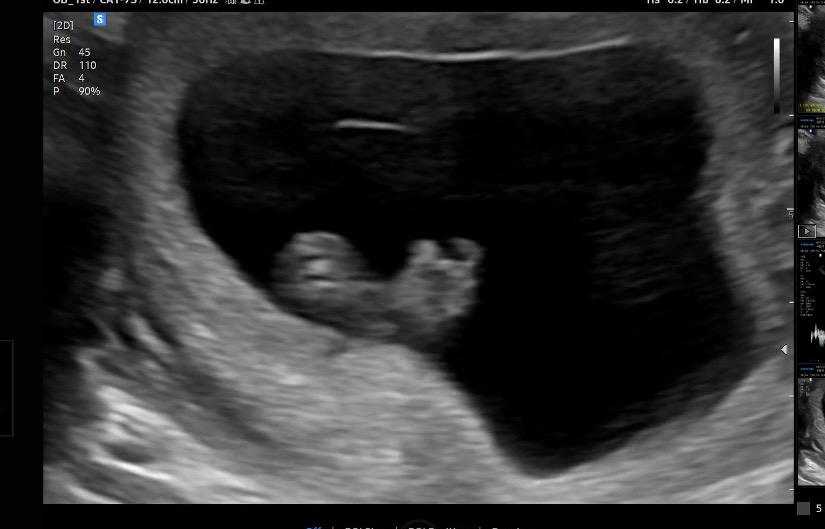

9주0일 초음파

어제 9주0일차 초음파 보고왔어요! 처음으로 복부 초음파로 봤는데도 잘보여서 너무 신기했어요. 젤리곰 기대했는데 아기가 옆으로 누워있어서 발까딱만 좀 봤네용. 근데 초음파 각도때문인지 문듯 라인? 이 보이는데 얼굴이랑 몸이어지는 부분이 너무 얇게(?) 보이더라구여 괜찮은거일까요??